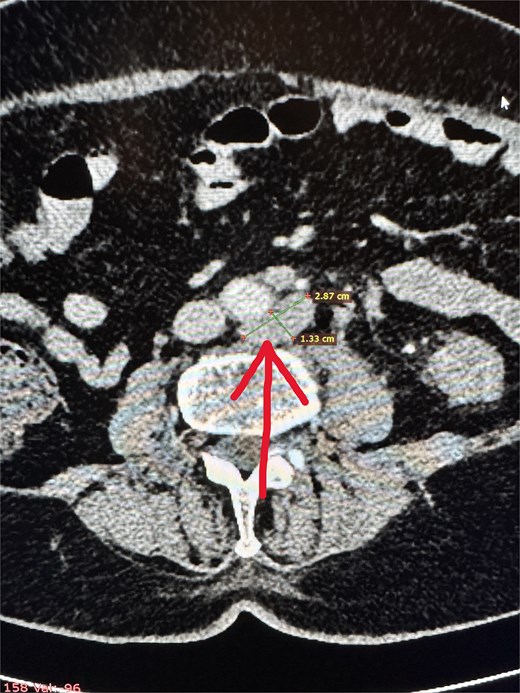

During surgery, the colon anastomosis was inspected and was macroscopically intact. A leak test was also negative. However, extensive adhesions were found around the pancreas, and the tail of the pancreas was enlarged with signs of necrosis. The pancreatic tail formed a conglomerate with the adjacent spleen area and the nearby colon. Intraoperatively, acute necrotizing pancreatitis with Balser’s fat necrosis was diagnosed. In the following days, the patient’s condition progressively deteriorated, with the development of multiple organ failure and sepsis. During the course of treatment, a urinary tract infection (Enterococcus faecium) and fulminant kidney failure occurred. Additionally, on the fifth postoperative day, infection of the laparotomy wound (Klebsiella pneumoniae) was diagnosed. Despite aggressive management and broad-spectrum targeted antibiotic therapy, the infection progressed to sepsis and the patient died (Table 1).

traction with surgical hooks leading to compression of the pancreatic duct and ischemia of the pancreatic tail,

mobilization of the splenic flexure of the colon [3],